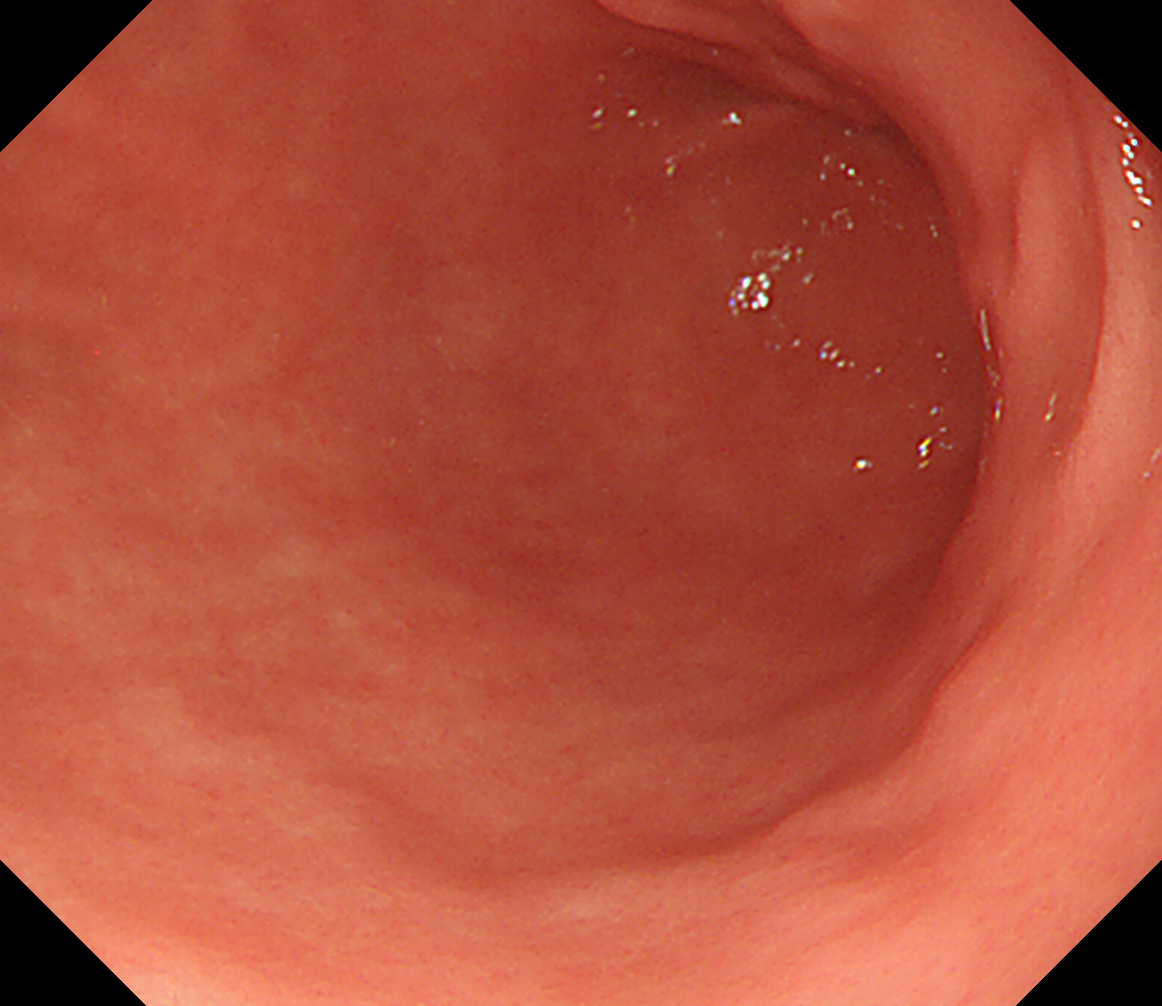

23 胃角部大弯 以下ずっと[見下ろし]でくるくる反時計方向に回しながら引き上げていく

萎縮境界の観察なども行います

胃角部大弯

24 体下部後壁 引き上げて

後壁から反時計回り

接線になり見逃しやすい部位です

体下部後壁